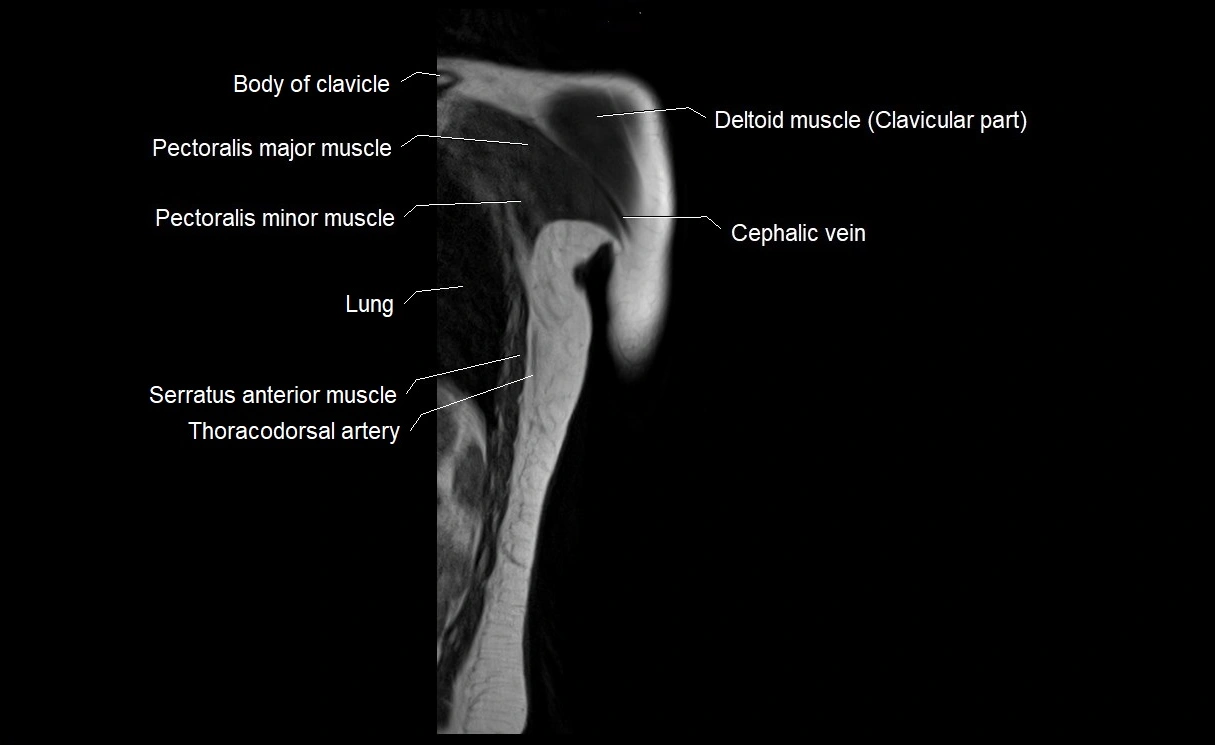

- Clavicle

- Clavicular part of deltoid muscle

- Pectoralis major muscle

- Pectoralis minor muscle

- Shaft (body) of clavicle